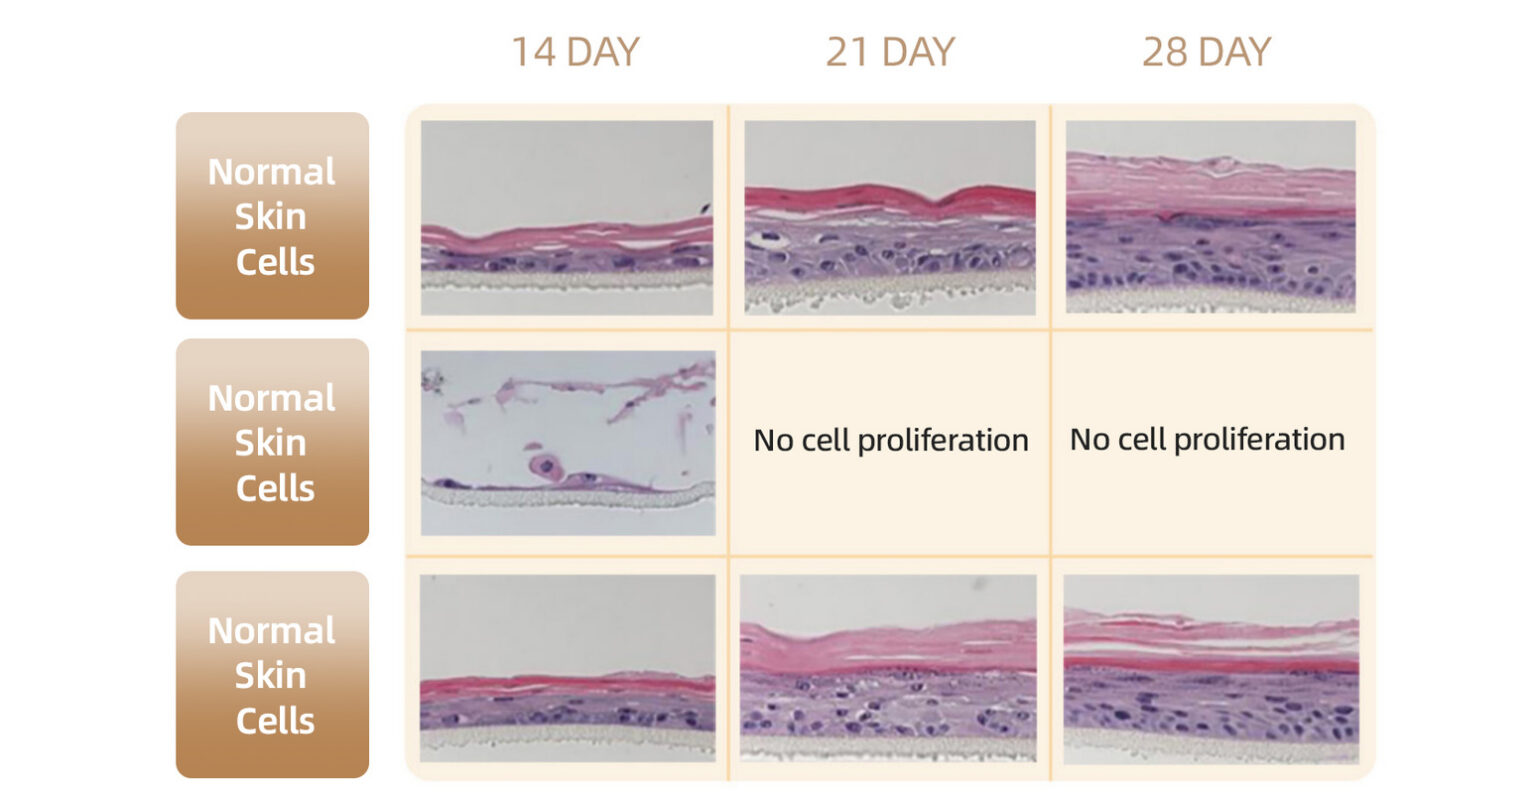

VTR Tissue Regeneration Patent Technology

First in the world to unlock tissue regeneration potential · Successfully achieves skin cell rejuvenation. One Round of Cell Renewal, 10 Years Younger Skin.

28 days to restore youthful skin

Transforms in 4 weeks